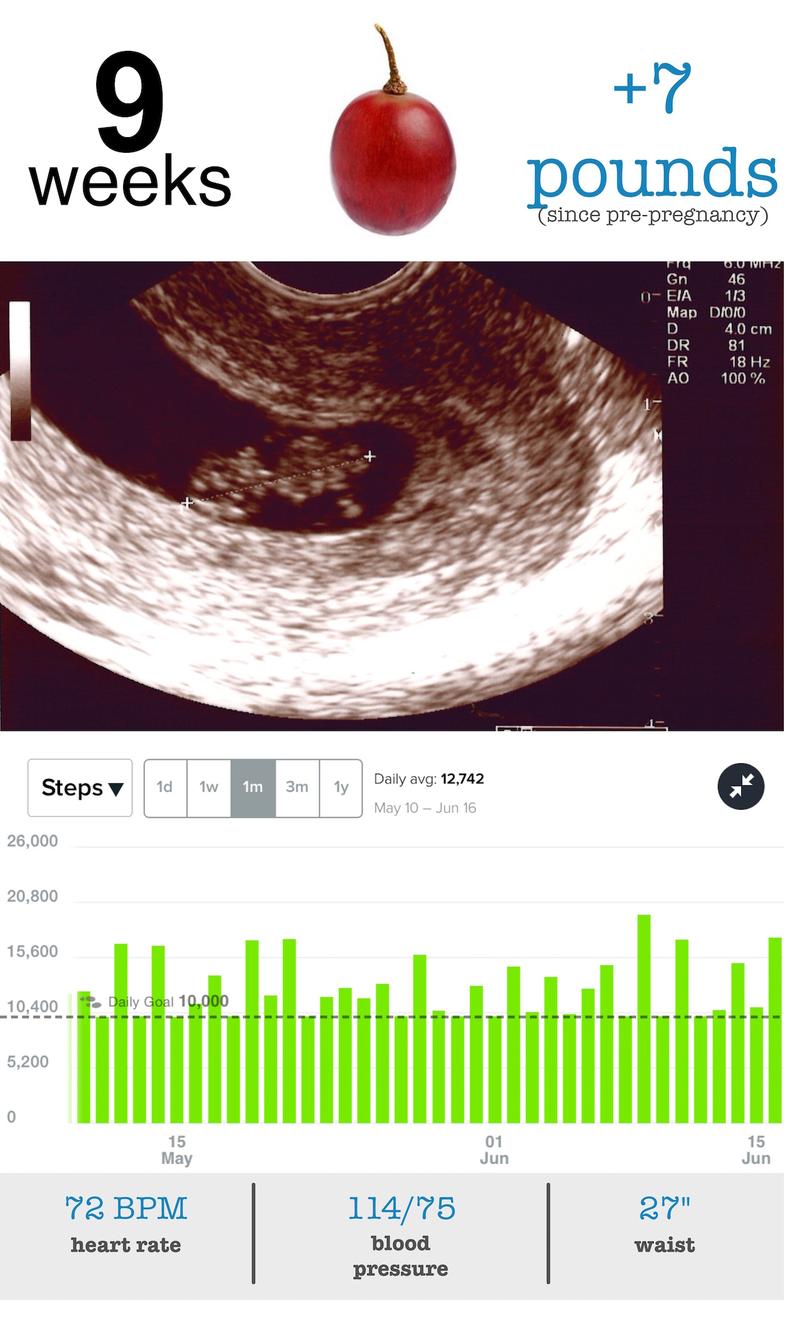

Pregnancy - 9 Week Update

- baby size: grape

- my size: +7 pounds - Although I’ve put on 7 pounds my regular clothes still feel comfortable.